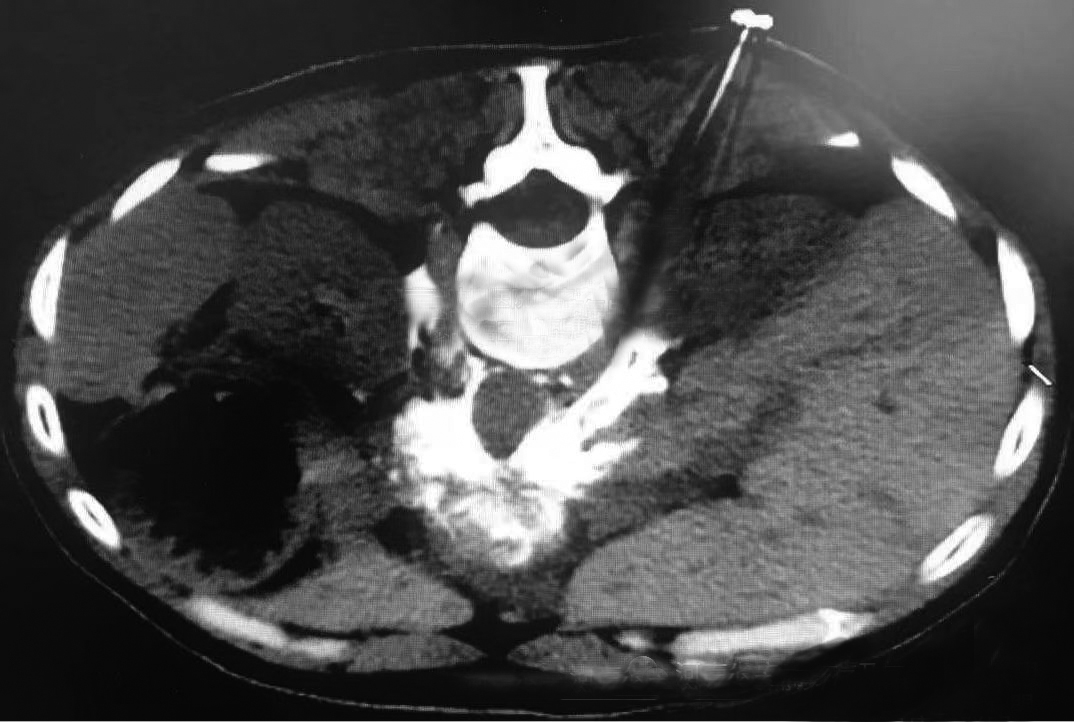

CT引导下腹腔神经毁损是治疗癌性腹痛的方法之一。这种技术仅用两根直径0.5毫米的穿刺针,精确地将针尖穿刺到导致腹痛的责任神经丛——腹腔神经丛周围,然后注入药物破坏神经传导,从而消除疼痛。但是,在常规的腹腔神经丛毁损过程中,没有对肿瘤进行治疗,甚至肿瘤一直在生长,导致止痛有效率低(仅为70%左右),或者虽然有效但是很快又出现疼痛。针对这种情况,谢广伦团队通过深入研究,开展了“腹腔神经丛毁损联合肿瘤内毁损药物注射”技术,在进行神经毁损的同时把毁损药物注射到肿瘤内部。在止痛效果更好(有效率可提高到90%左右)的同时,肿瘤也在药物的作用下缩小、坏死或失活,因此病人的生活质量更好,存活时间更长。

据谢广伦介绍,CT引导下腹腔神经毁损特别适用于胰腺癌、胆管癌、肝癌、胃癌和其他癌症腹膜后转移导致的癌性腹痛及胸背痛。CT引导下腹腔神经丛毁损创伤小,止痛效果好,又能减瘤,适用于部分体质较差的患者,建议在肿瘤转移早期应用。应用越早,止痛效果和肿瘤控制效果越好。